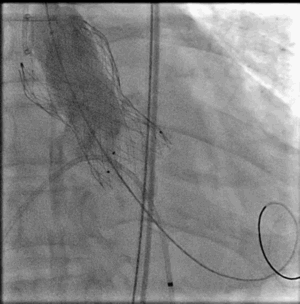

继续释放完瓣膜,注意三个T头脱勾后撤出输送系统,交换猪尾到心室,进行根部造影

根据支架形态,此次选择BaIt23球囊后扩

瓣膜释放完成左右冠显影良好 瓣膜最终形态

L26号瓣膜释放,BaIt23预后扩,几乎无瓣周漏,压差解除